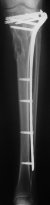

Молодой женщине по поводу бамперного перелома через 2 недели после травмы выполнен остеосинтез большеберцовой кости гвоздем ChM в одной из больниц Москвы. Снимок приложен. Сейчас речь пошла об удалении гвоздя и остеосинтезе пластиной. Действительно ли это оптимальный план? Какие есть еще варианты?

A female 24 years old, a sister of a friend of mine (not physician) living in Moscow, 3 weeks ago admitted to the hospital in Moscow after a car accident (was a pedestrian) with a tibial shaft fracture. 3 days ago closed locked nailing was performed, see attached films. Now he is in panic because they are going to remove the nail and perform plating.

The tibia shaft fracture (proximal 1/3 of the shaft) is apex medial 20 degrees, slightly short and a few degrees apex anterior after nailing. The nail extends quite proximal to the entry site. I wasn't able to see the distal end of the nail on my screen and am not certain if there was distal locking.